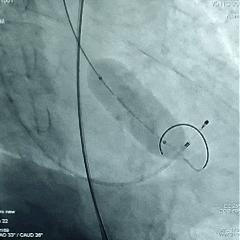

瓣膜工作位评估

瓣膜工作位多角度评估

瓣膜稳定脱钩

瓣膜脱钩后造影,瓣膜形态不佳决定后扩张

20mm球囊后扩张

瓣膜后扩后造影测压,无压差